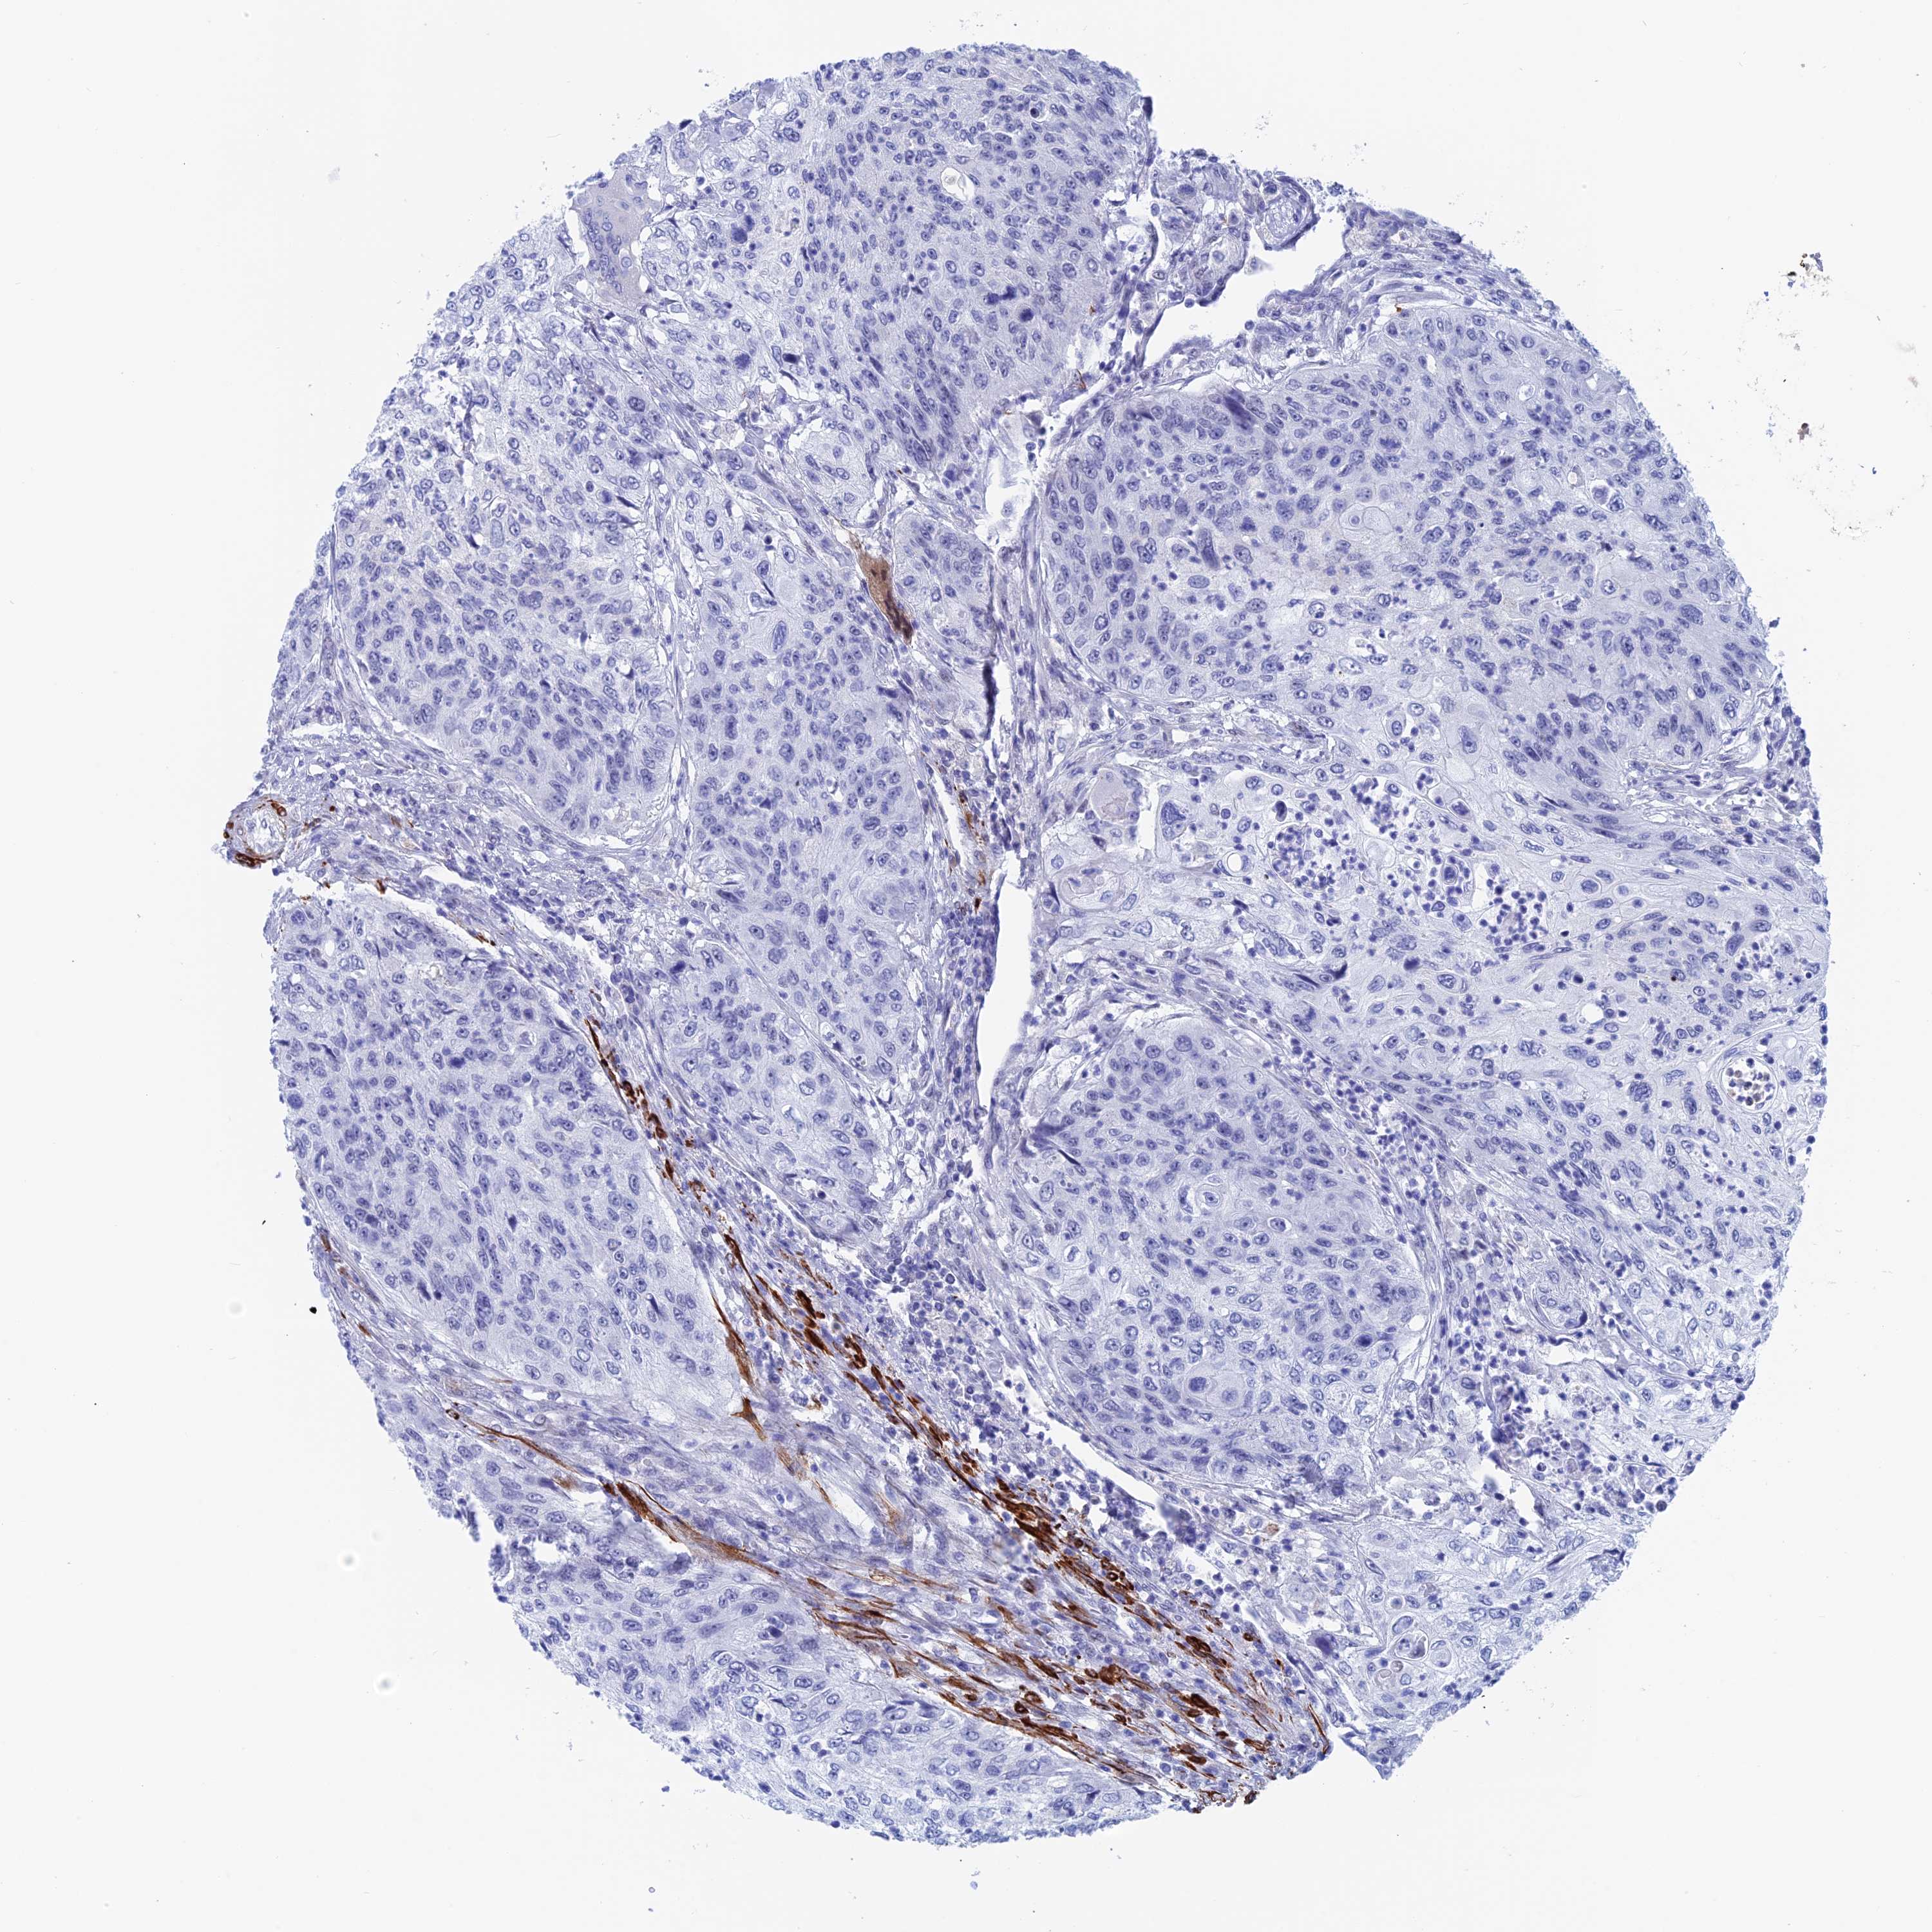

UROTHELIAL CANCER - Protein expressioni

A mouse-over function shows sample information and annotation data. Click on an image to view it in a full screen mode. Samples can be filtered based on level of antibody staining by selecting one or several of the following categories: high, medium, low and not detected. The assay and annotation is described here.

Antibody stainingi

Antibody staining in the annotated cell types in the current human tissue is reported as not detected, low, medium, or high, based on conventional immunohistochemistry profiling in selected tissues. This score is based on the combination of the staining intensity and fraction of stained cells.

Each image is clickable and will lead to virtual microscopy that enables deeper exploration of all samples and also displays staining intensity scores, fraction scores and subcellular localization as well as patient and tissue information for each sample.

Antibody HPA042629

Antibody HPA042838

Staining

High

Medium

Low

Not detected

Intensity

Strong

Moderate

Weak

Negative

Quantity

>75%

75%-25%

<25%

None

Location

Nuclear

Cytoplasmic/membranous

Cytoplasmic/membranous,nuclear

Urothelial carcinoma, High grade

Urothelial carcinoma, Low grade